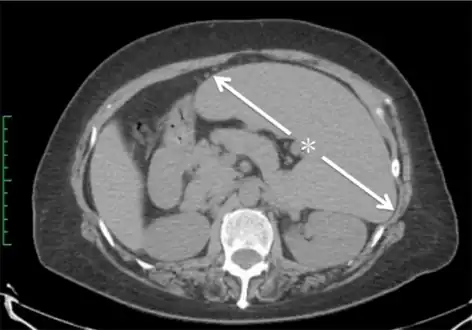

Computed tomography shows a massively enlarged spleen ( splenomegaly). -

Abdominal CT is the most accurate and spleen need to be larger 2-3 times to be palpable below the costal margin in physical examination that can help in diagnosis.